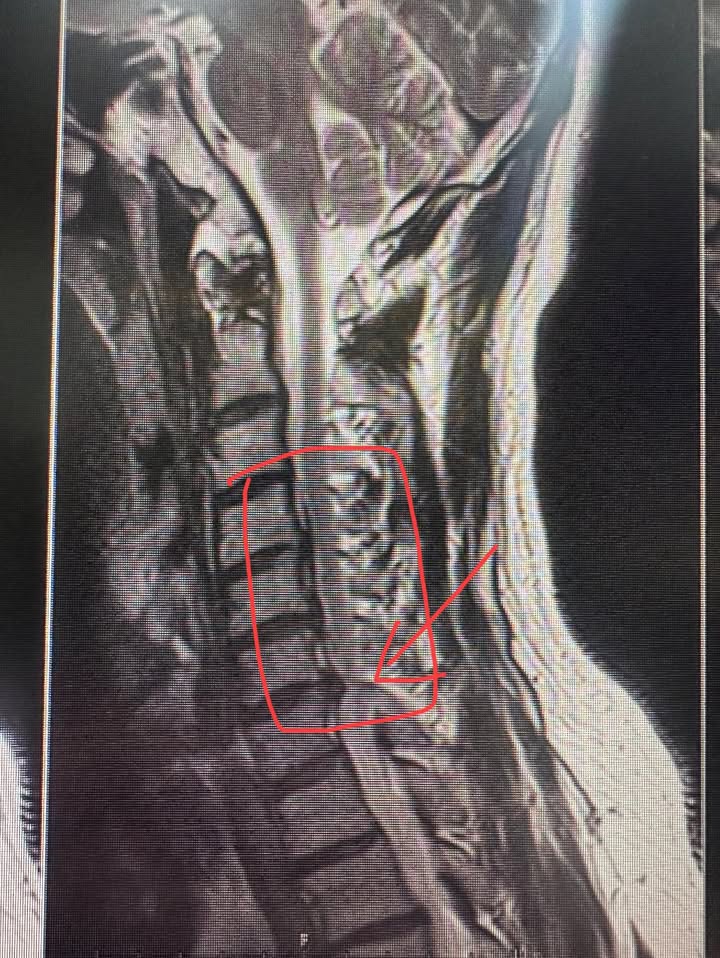

3. 病理變化:

• 第二張影像中特寫展示了可能的椎間盤突出,特別是在C5-C6和C6-C7處,這些部位的椎間盤突出可能引起脊髓或神經壓迫,進而導致臨床症狀。

評估:有壓迫!但還沒有到手腳無力,開刀暫時緩緩,雖然患者已經表示大醫院已經準備叫他開刀